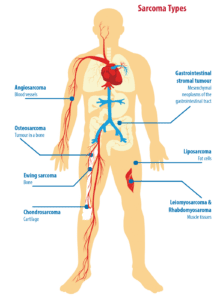

A sarcoma is a rare type of cancer that develops in connective tissue. Sarcomas can develop in a variety of tissues such as bone, soft tissues, fat, muscle, nerves, fibrous tissues, blood vessels and deep skin tissues. They most often develop in the limbs, but can be found in any part of the body. A common question for individuals who are diagnosed with a sarcoma is what caused it to develop?

While most cases of sarcoma are caused by damage from our environment, lifestyle, and the normal aging process (also known as sporadic or cancer by chance), some are inherited meaning the risk of getting a sarcoma is passed from one generation to the next through our genes. There are several known genetic conditions that are associated with an increased risk of sarcoma. Some of these genetic conditions include Li-Fraumeni syndrome, Familial Adenomatous Polyposis, and Neurofibromatosis Type 1.

While most cases of sarcoma are caused by damage from our environment, lifestyle, and the normal aging process (also known as sporadic or cancer by chance), some are inherited meaning the risk of getting a sarcoma is passed from one generation to the next through our genes. There are several known genetic conditions that are associated with an increased risk of sarcoma. Some of these genetic conditions include Li-Fraumeni syndrome, Familial Adenomatous Polyposis, and Neurofibromatosis Type 1.